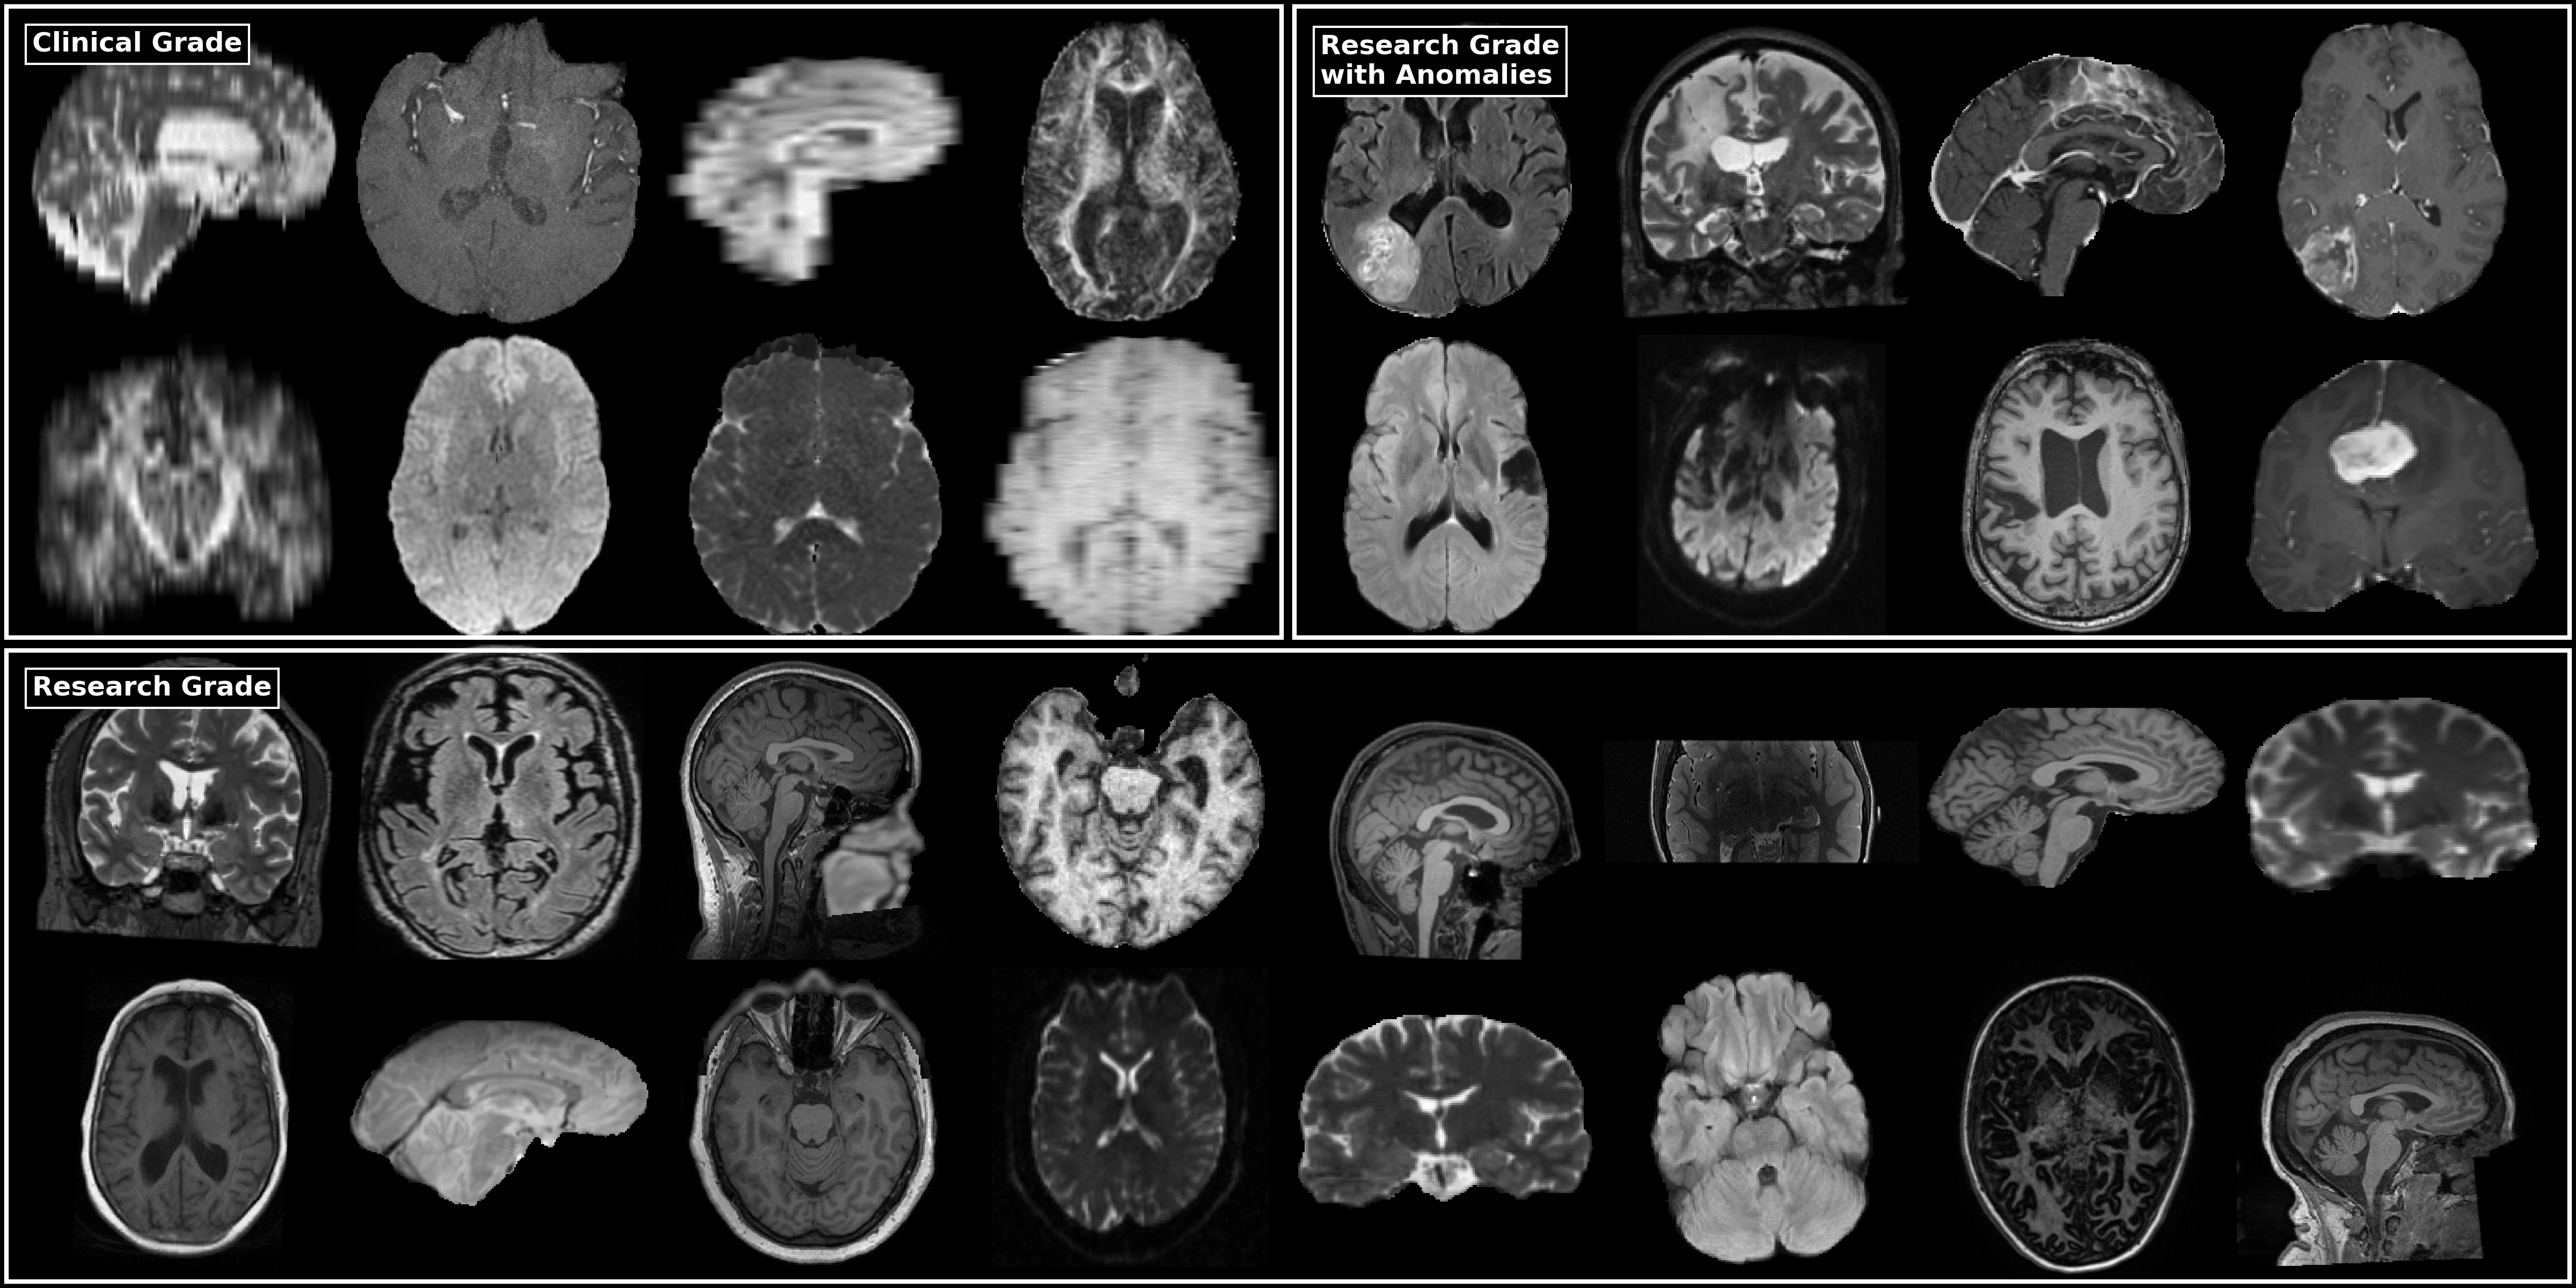

In the last decades, Magnetic Resonance Imaging (MRI) has become a central tool in brain clinical studies. Most of these studies rely on accurate and